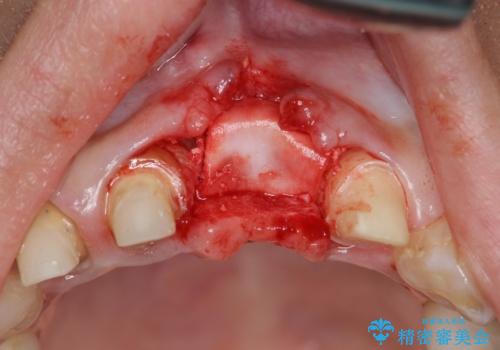

不良インプラントを除去し最終的にブリッジによる補綴で審美性の改善を行うこと、その準備として骨の造成・歯肉の移植による歯の欠損部顎堤のボリュームを維持・増大を計画します。

感染したインプラントからは排膿が間欠的に認められ、掻爬・除去が検討されうるような状況でした。

より審美的な改善を強く求められたため、インプラントを除去し可及的に欠損部顎堤を増大したのちブリッジによる審美改善を行いました。